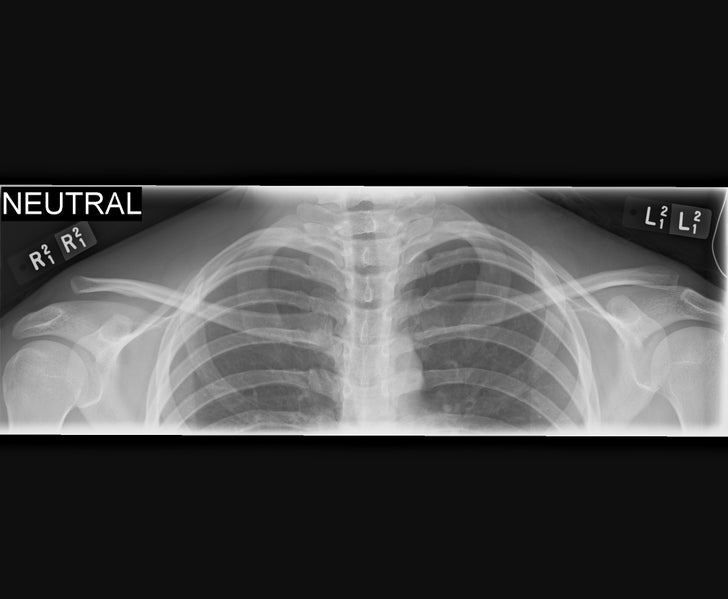

On the other hand, the most common variety (Type III) includes complete rupture of both ligament complexes (FIGURE 1: A & B); entirely disconnecting the collarbone from the shoulder blade. Without the support of the clavicle, the weight of the upper extremity pulls the scapula down, further separating the two bones and leading to the characteristic xray findings (FIGURE 2). Rarely, the end of the clavicle can actually poke through or become entrapped within the muscles of the shoulder (Type IV).